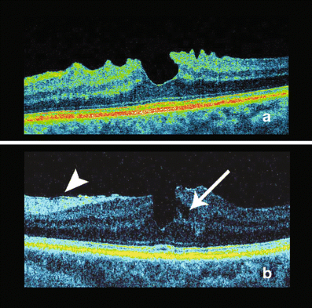

In 6 months of follow-up in case 1 and 2 months in case 2, MPH progressed to non-full-thickness macular defect, fulfilling the criterion of LMH in SD-OCT. Non-vitreous interface traction was detected.

SD-OCT proves that MPH may progress to LMH without any vitreous traction. Progressive contraction of epiretinal membranes may be a cause of both MPH and LMH, being an advanced stage of the same non-full-thickness macular disorder.

Fig. 1

Fig. 2